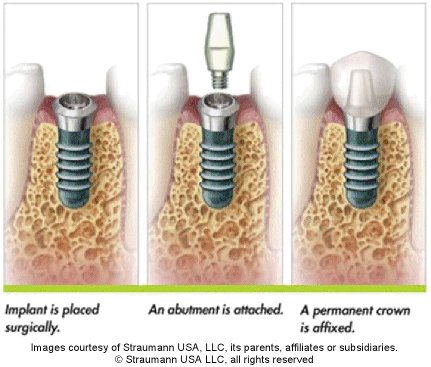

In the case of a missing single tooth, once the bone has integrated with the implant (from 8 weeks to 6 months) an abutment is attached to the implant and a crown can then be seated on the abutment, to replace the missing tooth.

A dental implant is a medical grade titanium fixture that is placed gently into bone. When the bone has united with the implant, an impression can be taken in order to provide a crown which can then be connected to the implant. The crown is connected to the implant by means of an abutment. Dental implants are used to allow replacement of one or more missing teeth.